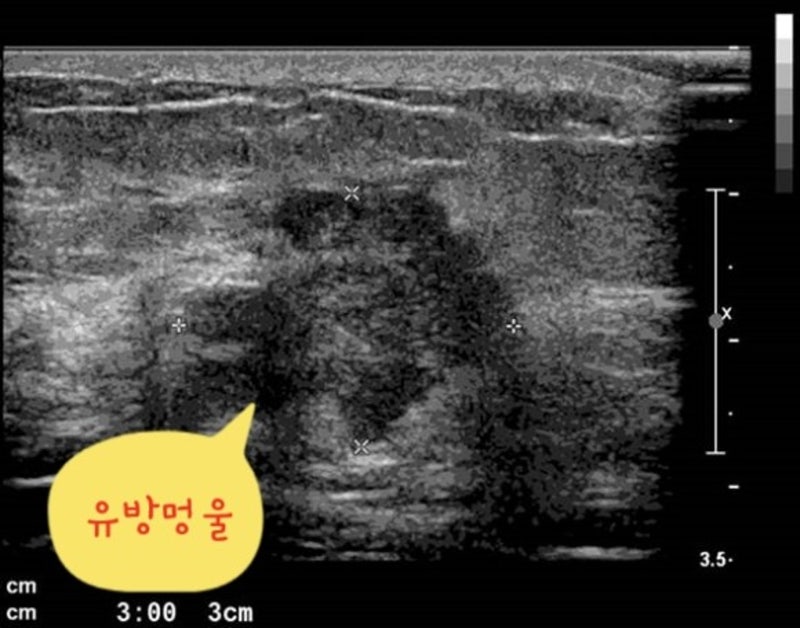

겨드랑이의 선 조직에서 종양이 발생하여 겨드랑이에 덩이의 감각을 유발할 수 있습니다. 유방 종양이 발견되면 대부분의 사람들은 유방암에 대해 먼저 걱정합니다. 대부분의 유방 또는 양성 종양은 일반적으로 비암성으로 진단됩니다. 그러나 일부 경계성 종양은 양성과 악성의 구분이 어렵거나, 양성 종양의 경우 크기나 모양이 좋지 않아 절제가 필요하므로 적절한 치료가 필요합니다. 4_ 유방암

겨드랑이의 덩어리는 때때로 유방암으로도 알려진 악성 종양으로 식별됩니다. 대부분의 유방암은 초기에는 무증상이어서 조기 발견 시기를 놓치는 경우가 많다. 유방암은 조기 발견에 따라 생존율이 달라지기 때문에 겨드랑이에 혹이나 혹이 느껴진다면 가능성을 열어두고 빨리 진찰을 받는 것이 최선이다. 겨드랑이에 혹이나 혹이 생겼다고 바로 유방암이나 주요 질환을 의미하는 것은 아니지만, 유방암 발병률이 증가함에 따라 질병을 조기에 발견하고 신속하게 대응하여 치료의 부담을 덜 수 있기를 바랍니다. 서울특별시 서초구 서초대로77길 3 아라타워 1206호 유정갑 수술실